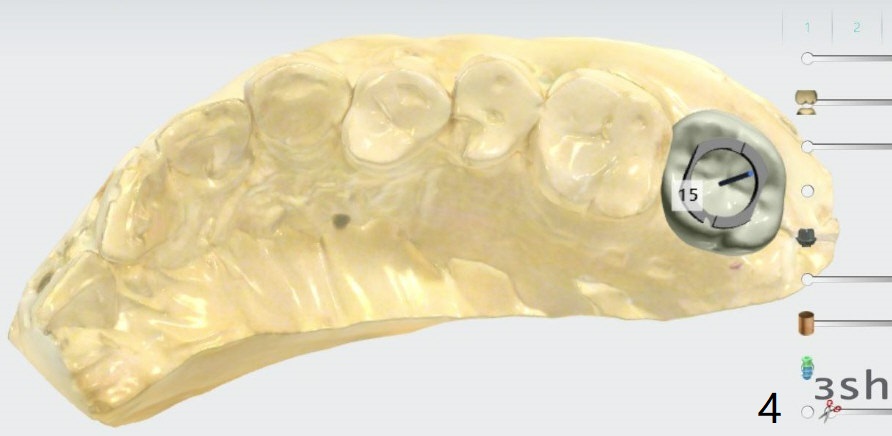

No Sinus Lift

Return to No Deviation